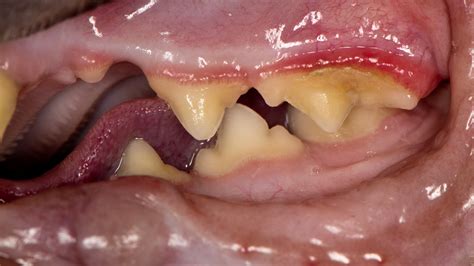

Gingivitis In Cats

Did you know that cats also suffer from gum disease? The most common type in cats is called gingivitis. Humans and dogs also get this gum disease, but it tends to be more severe in cats. The symptoms ...

Gingivitis in cats is one of the most common dental problems seen in general practice, yet it’s often misunderstood or missed by owners until the condition becomes severe. As a small animal vet with ...

Gingivitis is early stage gum disease. It happens when plaque and bacteria build up on your teeth. Common symptoms include red, swollen, bleeding gums.